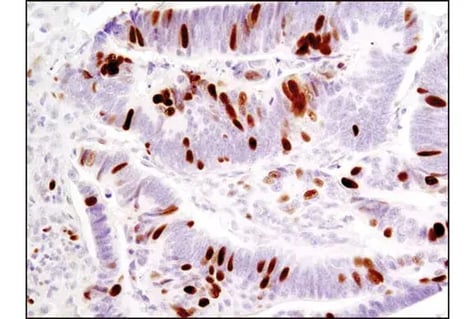

IHC analysis of paraffin-embedded human ovarian serous papillary carcinoma using p16 INK4A (F9T1L) Rabbit Monoclonal Antibody #88667.